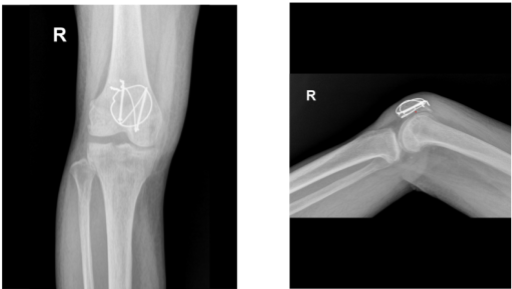

Case Study: Open Reduction Internal Fixation: Closed Fracture of Patella in a 73 year-old woman

The patient, a 73 year-old woman, was diagnosed with an displaced fracture of the patella on the right side after the doctor examined her about a month ago. She received conservative care while wearing a knee brace.

She put a lot of effort into her home, especially during the flooding, and in the process she dislodged the patella fracture. When I saw her again in my office, we discovered that she had a dislocated patella fracture.

X-ray Image right knee

The fracture received a thorough irrigation. The fracture was reduced and secured with a clamp. After creating a short vertical incision to the patellar tendon, two K-wires were transferred from the distal bone to the proximal bone once the fracture was securely stabilized. After measuring the K-wires, two cannulated cancellous screws were medially and laterally placed over the K-wires to accomplish fixation.

The anterior patellar surface was then perforated by making a figure-eight with an 18-gauge stainless steel wire after it had been threaded through the two screws. The wires were tied super laterally with a knot that was secured.

Due to osteoporosis, there was some comminution and the lateral screw was moved proximally by the wire. A cerclage wiring was applied to the 18-gauge wire once more to support the fixing. A satisfactory fixation was attained once the cerclage was finished and the knot was tightened super laterally.